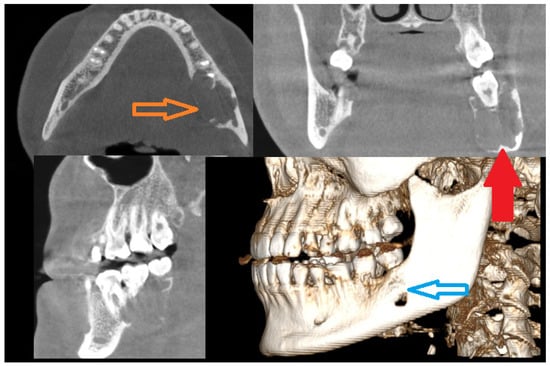

Figure 1. Cortical bone erosion and expansion might be a sign of a locally aggressive lesion (orange arrow, blue arrow). On the other hand, additional symptoms like tooth resorption, no signs of pathological fracture, and no lower lip numbness (lacking Vincent’s sign) could be helpful in tumor diagnostics. Irregular solid like mass with cortical spread and teeth resorption should be scheduled for a biopsy at first, since radiologically many primary, secondary, and even metastatic lesions can have a similar appearance [1,2,3]. Good CBCT (cone-beam computed tomography) improves the diagnostics when dental root status and possible odontogenic-related lesions are either confirmed or excluded. Symptoms alone do not influence the diagnostics; however, some atypical general coexisting patient conditions related to neurological symptoms (depression, tiredness, loss of concentration), excessive urination, loss of appetite and abdominal pain (nausea, vomiting), osteoporosis, muscle pain, and weakness followed by kidney stones and joint pains might be general symptoms manifesting primary hyperparathyroidism (PHP) cases, where some jaw tumors (brown tumor (BT), also known as osteitis fibrosa cystica) also occur [1]. In atypical jaw bone tumors, BT manifests in radiologically well-defined radiolucent areas with non-corticated borders and heterogenous radiolucent or radiopaque–radiolucent areas in the mandible bone. Secondly, teeth displacement, gum swelling, atypical periodontal status, and pain are present. PHP is related to endocrine disturbances caused by parathyroid hormone (PTH) overproduction. In most cases, the occurrence of a single adenoma, multiple adenomas, or, rarely, a carcinoma (1%) in the parathyroid gland is the main cause, with some female predominance. SPECT-CT (single photon emission computed tomography) and estimation of blood markers such as serum calcium, PTH levels, magnesium, triiodothyronine (T3), thyroxine (T4), thyroid-stimulating hormone (TSH), vitamin D, serum calcium, alkaline phosphatase (ALP), and phosphorus are sufficient to confirm PHP [2]. Magnesium, iron, or other ion levels are rarely investigated, but their role has never been fully elucidated. Quite often, parathyroidectomy causes all BTs to decrease, and the residual tumor sometimes requires some kind of surgical approach. On the other hand, a giant cell lesion of the jaw bones can also be present without any coexisting endocrine pathologies with a similar radiological and clinical appearance. A CGCG, central giant cell granuloma, is a benign, nonodontogenic lesion of the jaw, osteoclastic in origin, with unknown etiology mostly with asymptomatic painless swelling of the jaw bones (similar to that indicated by the red arrow). More advanced lesions tend to displace teeth and cause their resorption, and there is also a tendency for invading the oral mucosa after cortical bone thinning (red arrow) and perforation (blue arrow), with some bluish/brownish discoloration that might appear. Radiologically, they mostly present as radiolucent areas between the roots with a slow expansile character without any clear calcifications within and not uncommon extra-cortical bone spread (the approx. size of the longest axis of the CBCT image lesion was 45 × 34 × 28 mm) [1,2,3]. CGCG is mostly diagnosed through histopathological sample examination. In the presented case, this lesion was growing slowly over a long period of time. The radiological investigation was inconclusive, the blood examination for calcium–phosphate markers was not significant in this case, and biopsy was not indicative of the diagnosis of any odontogenic tumors, cancers, or endocrine bone-related pathologies; however, a non-specific cystic appearance was found, and because of the following, a decision was made to perform radical surgery.

Diagnostics 15 02038 g001